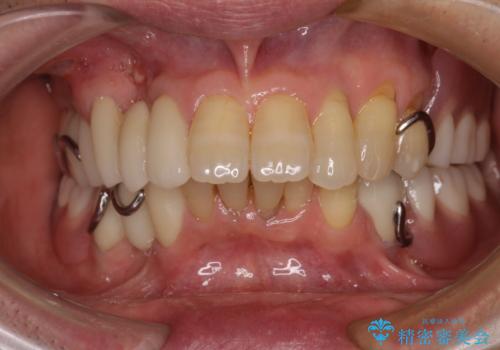

より適合の良い義歯とするため、セラミッククラウンなどは義歯の設計に合わせた土台の歯となるよう全て再製作をし、安定感に優れた義歯を製作することができました。